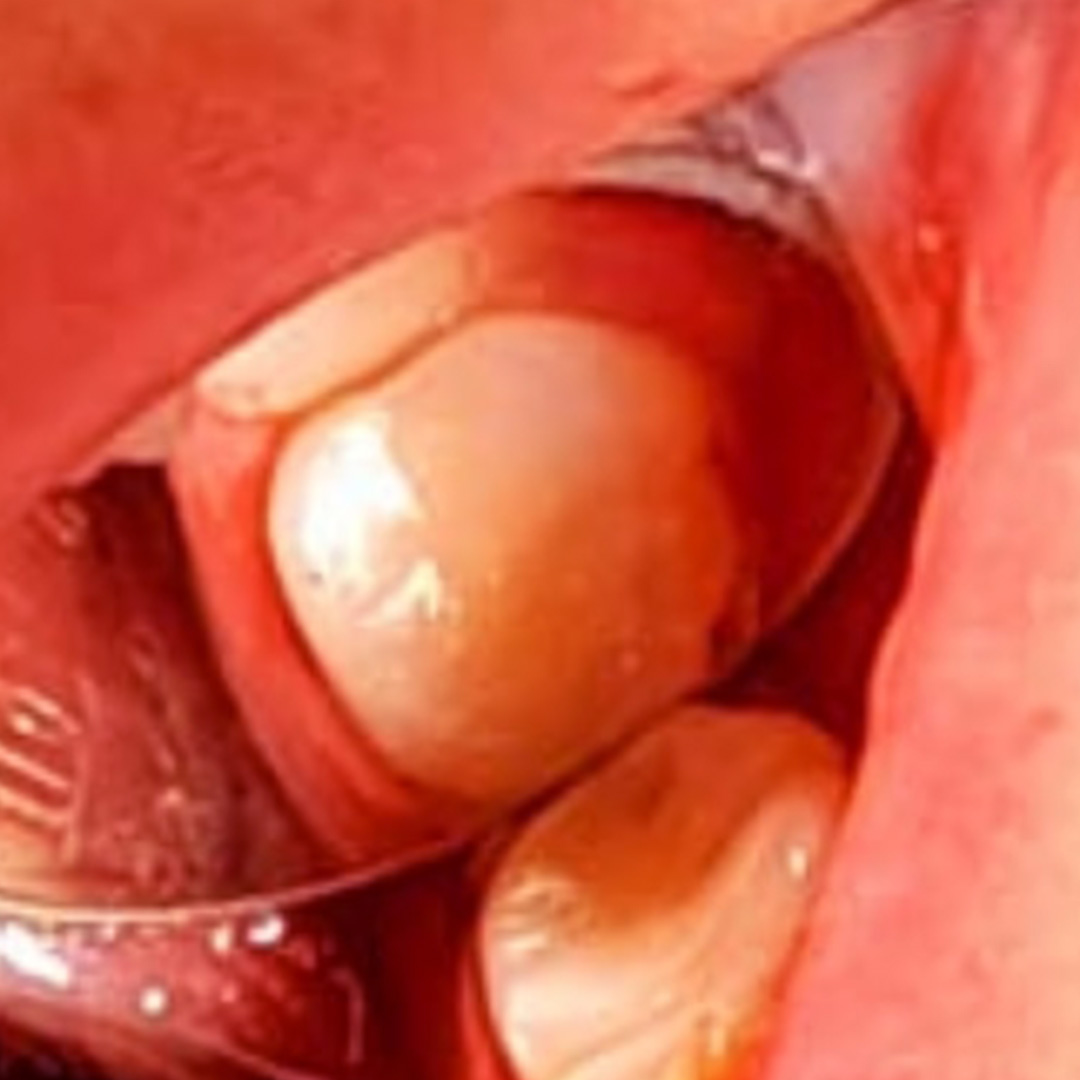

Пациентка обратилась в стоматологию с жалобами на выпадение пломбы из зуба мудрости в нижней челюсти и резкую, быстро проходящую боль от холодной пищи. Врач Похилько Надежда Геннадьевна провела осмотр, в результате чего поставила диагноз — глубокий кариес зуба 38. После согласования с пациенткой проведено лечение с использованием композита светового отверждения Estelite.

Ход лечения:

- удаление налёта и камня с поражённого зуба;

- проведение анестезии;

- механическая и медикаментозная обработка;

- формирование полости для плотного прилегания пломбы;

- нанесение светокомпозита Эстелайт;

- воздействие УФ-лучей для затвердевания пломбы;

- полировка зуба.